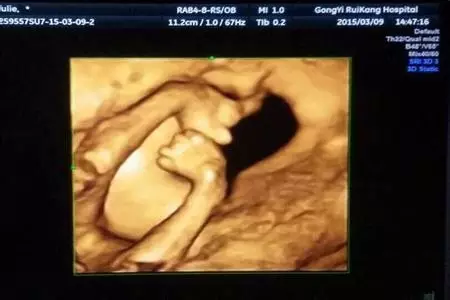

四维彩超 见证生命最初的感动

瞧,他对我笑了!看,她在伸懒腰!哦,这个调皮鬼是在做鬼脸吗?

四维彩超不再单纯地感觉宝宝的呼吸和运动,而是可以亲眼目睹他们在妈妈肚子里的一举一动。四维彩超满足了孕妇及家人对宝宝的好奇心理,让准爸爸们更早地对即将诞生的宝宝有了深厚的感情。越来越多的妇产科也允许孕妇家属陪同进入诊室观看栩栩如生的胎儿立体图像,从而提前知道胎儿在母亲腹中的生长发育状况和形态,满足母婴沟通的心理需要,让整个家庭共享生命最初的感动时刻。

四维彩超同时也使医生能够多角度、多方位地观察胎儿在腹中的发育情况,为早期诊断胎儿先天性体表畸开和先天性心脏疾病提供了准确的科学依据。